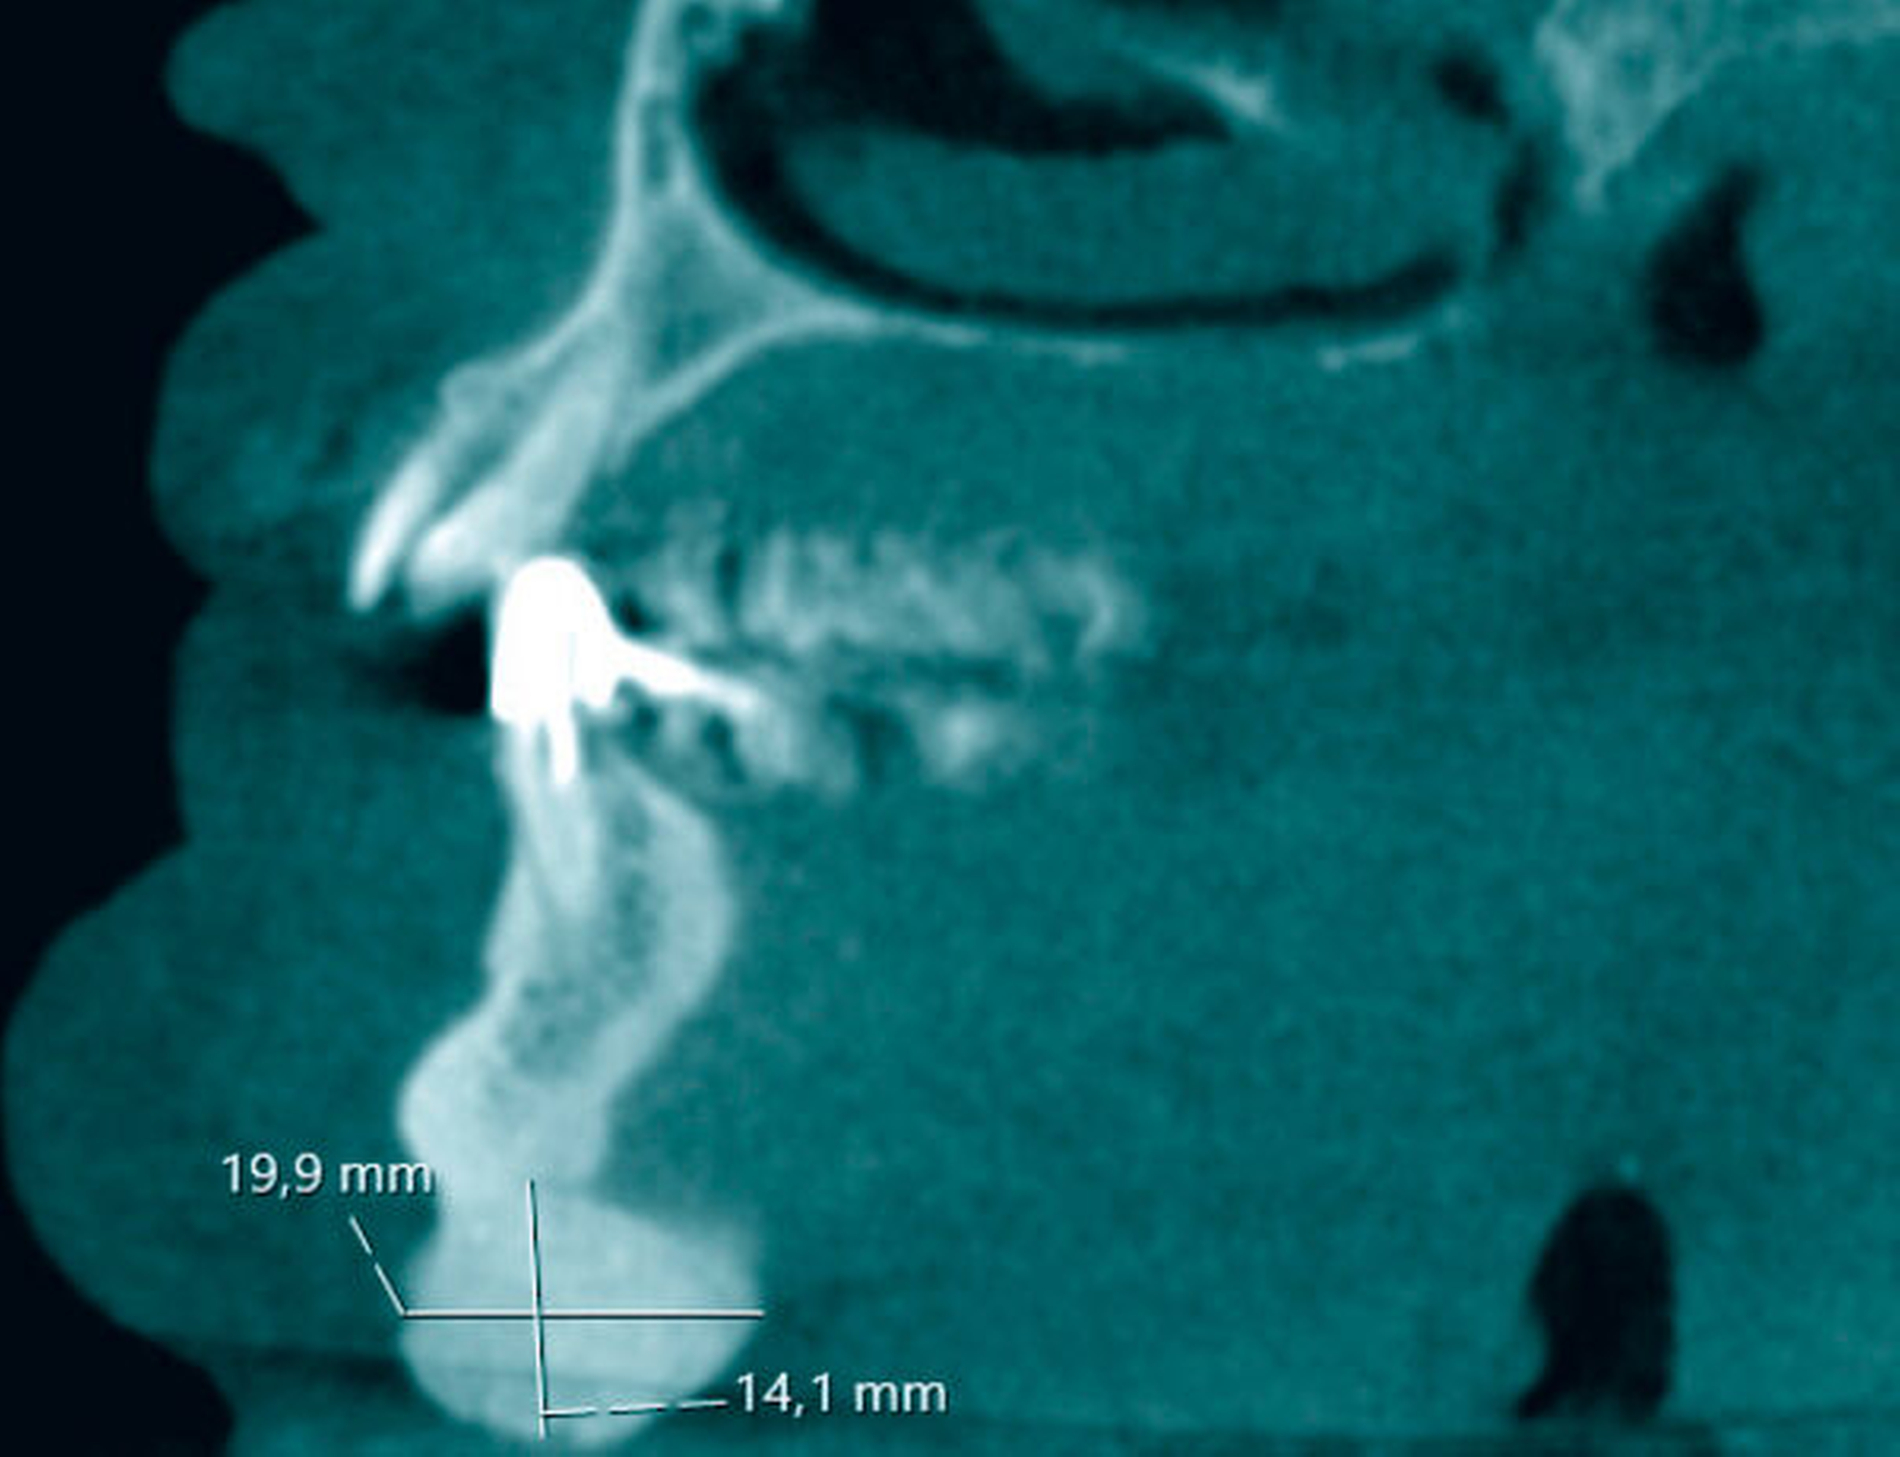

Die zur weiterführenden dreidimensionalen Diagnostik erstellte digitale Volumentomografie (DVT) zeigte eine 1,9 cm x 2,0 cm x 1,4 cm große, nodulär konfigurierte Raumforderung am basalen Unterkieferrand (Abbildung 3). Infolge der klinischen und der radiologischen Untersuchung wurde die Verdachtsdiagnose eines solitären peripheren Osteoms gestellt und der Patient über die geplante Befundexstirpation sowie die dabei bestehenden Operationsrisiken aufgeklärt.